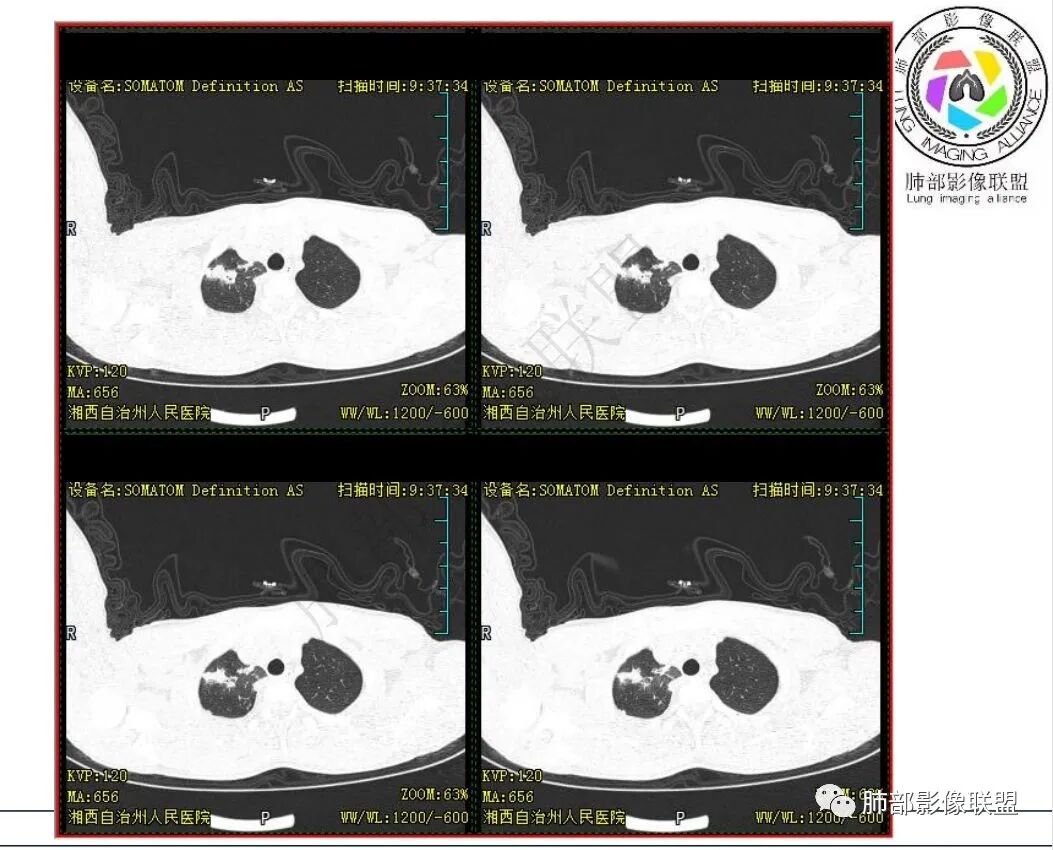

影像:右肺上叶多发实变影结节影,边界模糊,边缘收缩,伴多发空洞,洞壁光滑,部分支气管壁增厚。

3.首次CT提示:右肺上叶多发结节影及实变影,簇状分布,周围散在磨玻璃影,结节内多类圆形空洞,内壁光整,有一定张力,偶见液平。部分支气管壁增厚。

考虑良性感染性病变可能。